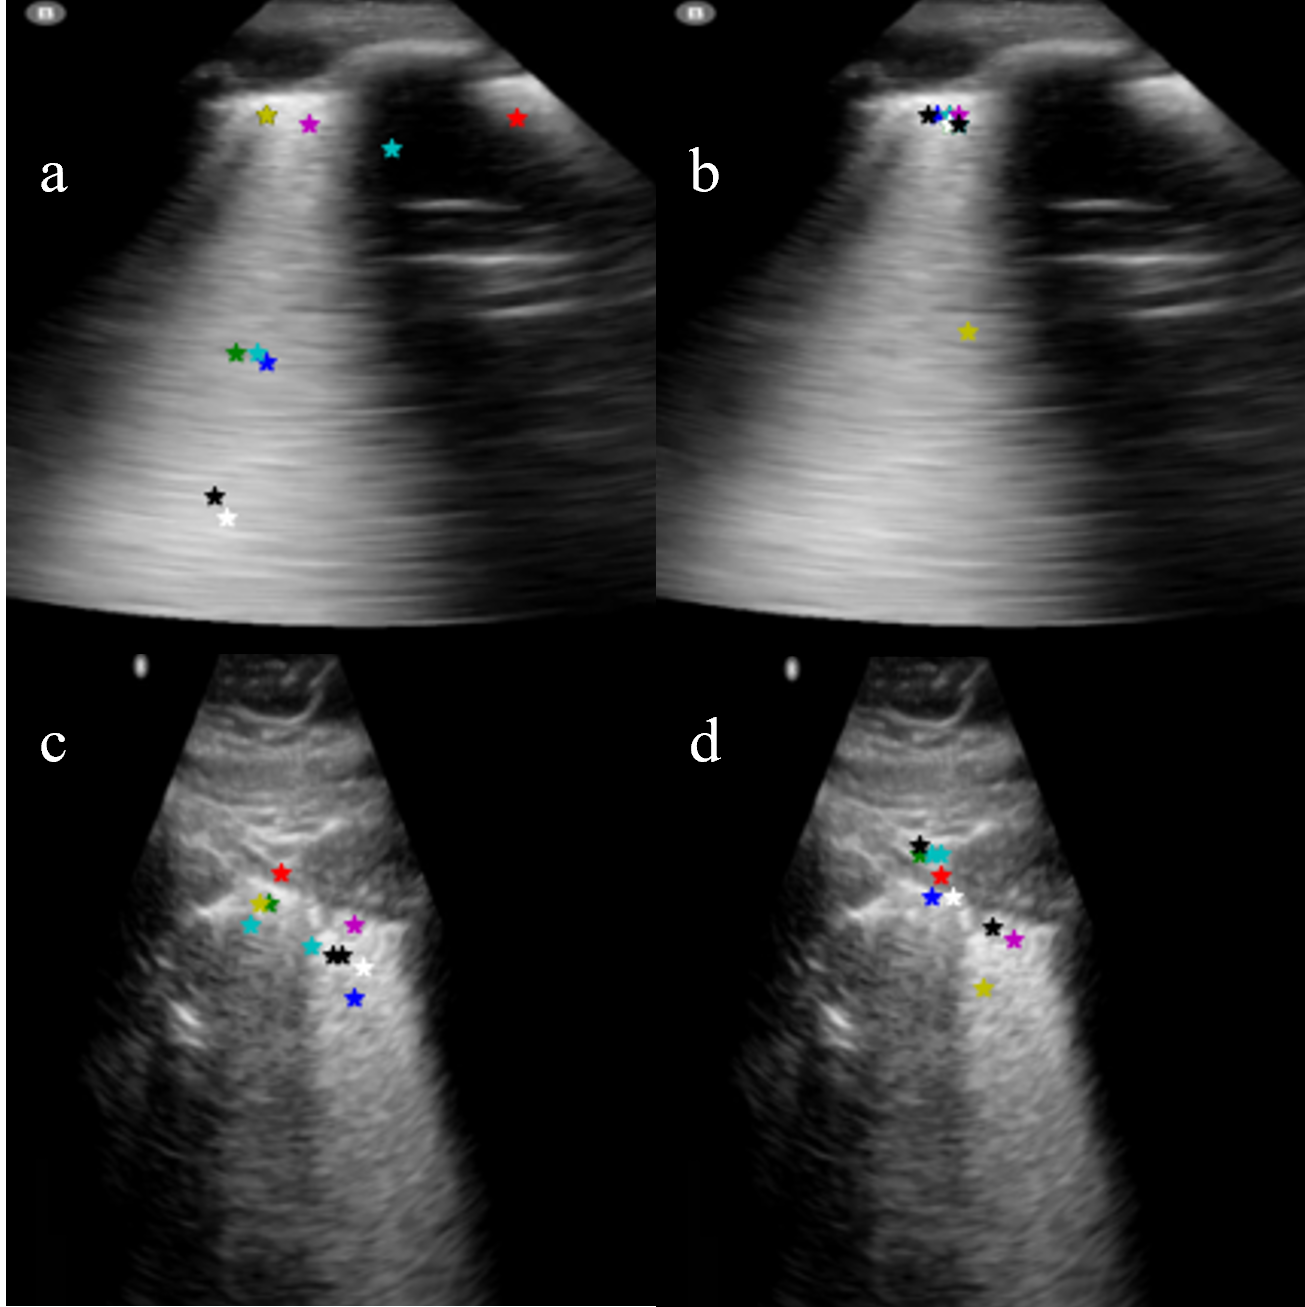

3.1.2 Effect of Radon transform

We used the Radon transform to enhance vertical and horizontal features and evaluated its effect on keypoints. As seen in Fig. 6 the Radon transform guides the automatically detected key-points towards commonly seen echogenic features in the image without any specific prior information on the intensity or location of the feature.

Refer to caption

Figure 6: (a) Without RT (b) With only horizontal IRT (c) With only vertical IRT (d) With both horizontal and vertical RT